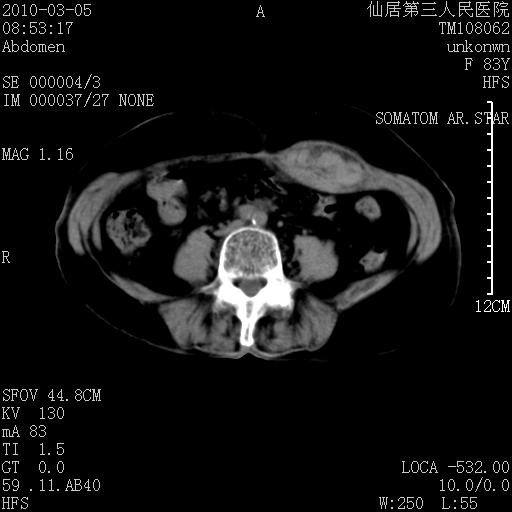

标题: CT24879:腹直肌病变。在线等。

女性,83y,腹痛一周。

支持腹壁纤维肉瘤

血肿,纤维瘤,子宫内膜异位都有可能。